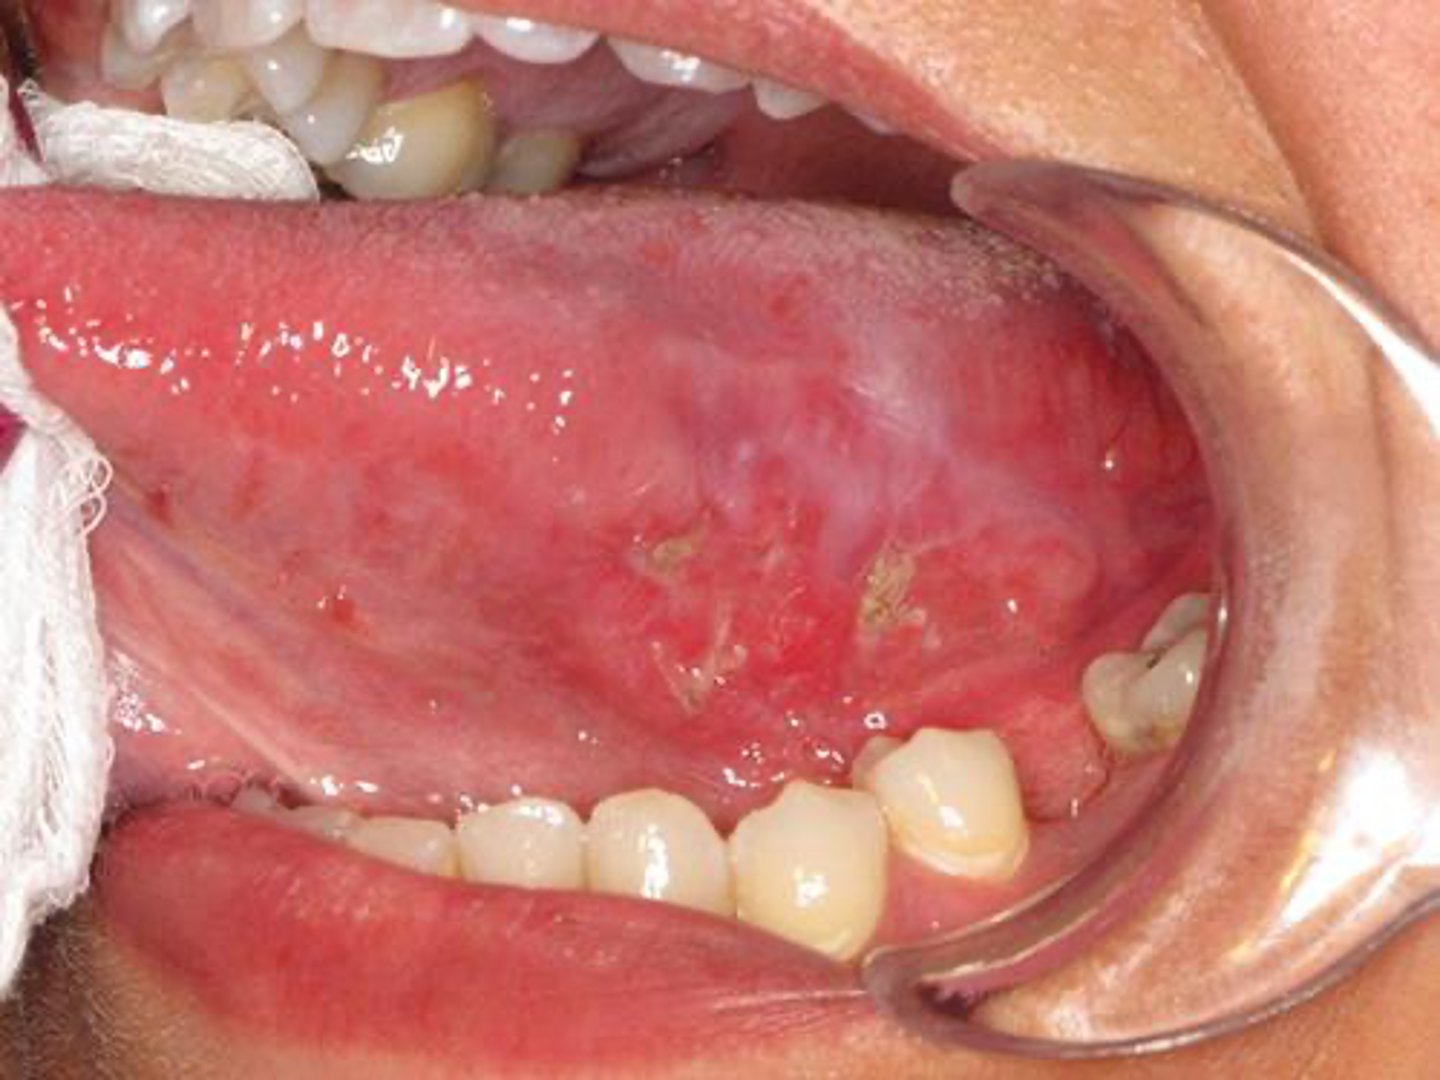

A patient presents with bilateral white lacy striations on the buccal mucosa.

What ist he most likely diagnosis?

lichen planus

A patient presents with a bilateral lacy striations on the buccal mucosa. The lesions are asymptomatic.

What is the most likely diagnosis?